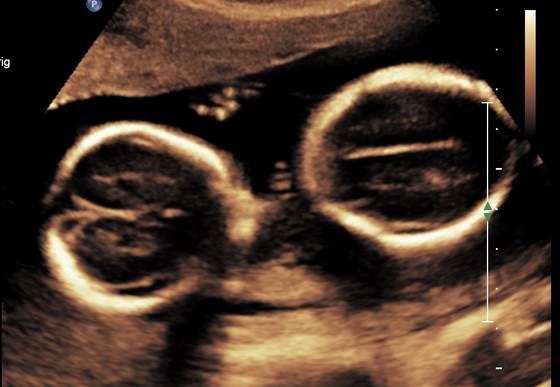

A wiec Dorotko moje szkraby maja lozyska obok siebie

Zobacz załącznik 718949